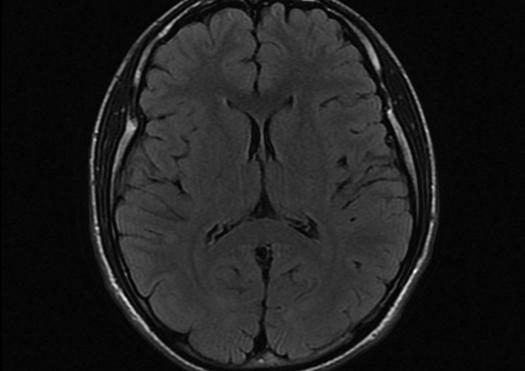

Resonancia Magnética (RM)

Resulta de la interacción entre el cuerpo del paciente, el campo magnético propio del equipo y ondas de radiofrecuencia que envía dicho equipo hacia los tejidos del paciente. Al cesar el envío de las ondas de radiofrecuencia desde el equipo, se producen nuevas ondas de radiofrecuencia en los tejidos, que se emiten hacia el equipo para la generación de imágenes.